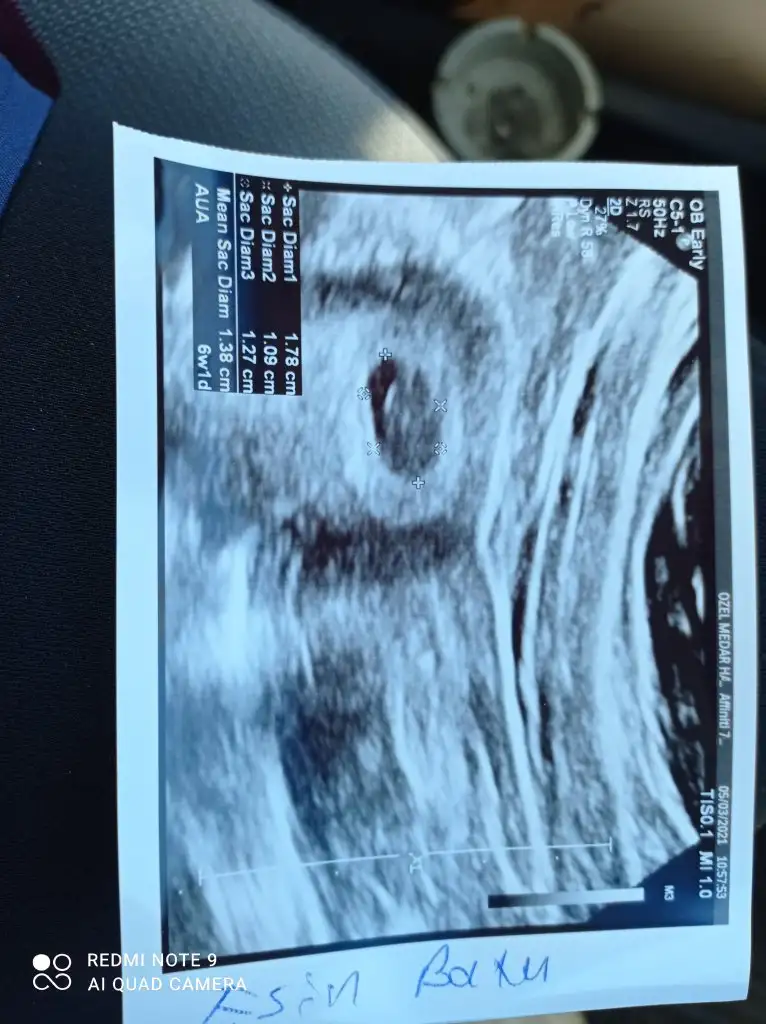

Şuan ikincı gebeliğm ve 6+4 kontrolle gittim

Kese var ama kalp atışı yok dedi doktor.

1 hafta sonra tekrar gel dedi.

Aynı durumu yaşayan var mı? Çok erken diye mi kalp atışı yoktu acaba?